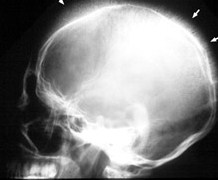

Q184) A 10 year old boy is evaluated in the emergency room after he tripped over and fell during a basketball game. There is no history of loss of consciousness. He denies any injury except some pain in the occipital area of the skull. He also reports chronic fatigue. A routine skull x-ray is obtained for evaluation and is shown below:

Which of the following is most likely to be associated with these incidental skull x-ray findings ?